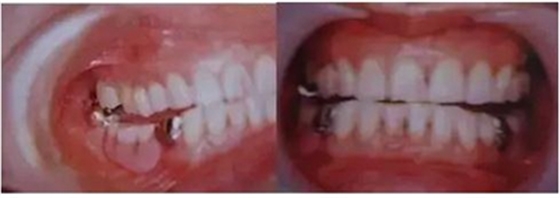

圖10. 不考慮下頜第三磨牙的咬合平面破壞的修復(fù)體制作完成后

后方磨牙干擾引發(fā)的前方誘導(dǎo)干擾。